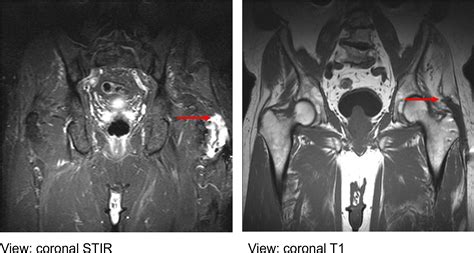

Gluteus Medius Tendonitis Treatment - Centeno-Schultz Clinic

Gluteus Medius Tear Treatment in Columbus, OH | OrthoNeuro